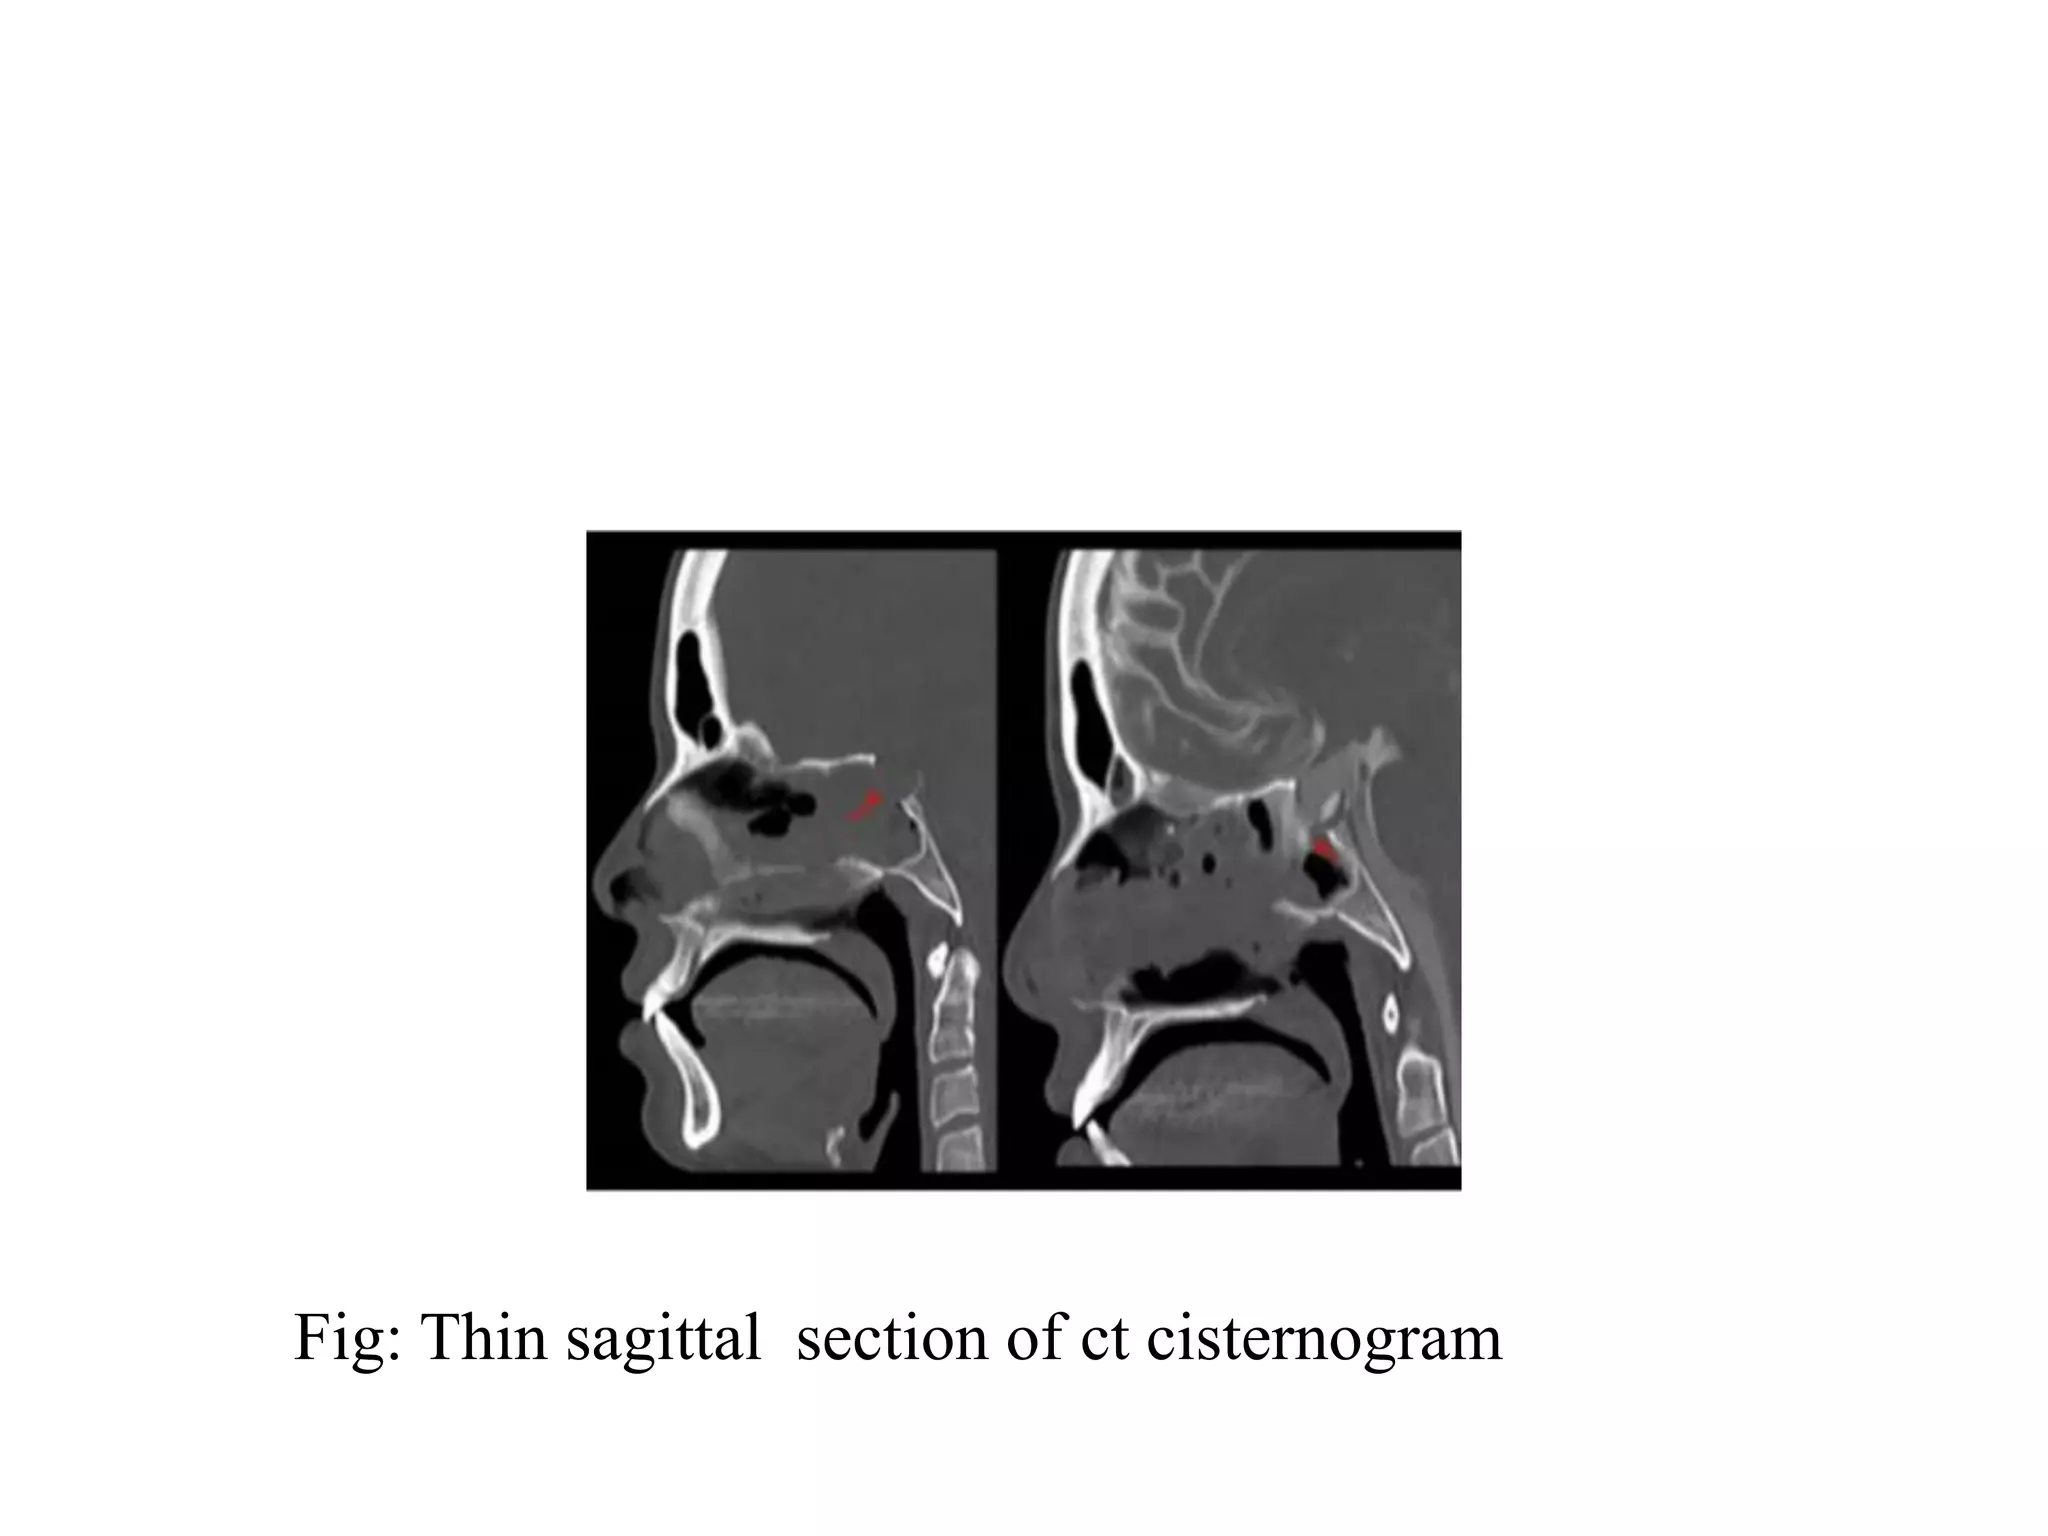

Fig: Thin sagittal section of ct cisternogram

Fig: Thin sagittalsection of ct cisternogram